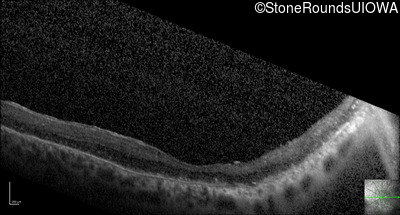

Optical Coherence Tomography - Right - 10/200

Exemplar / OCT Stack